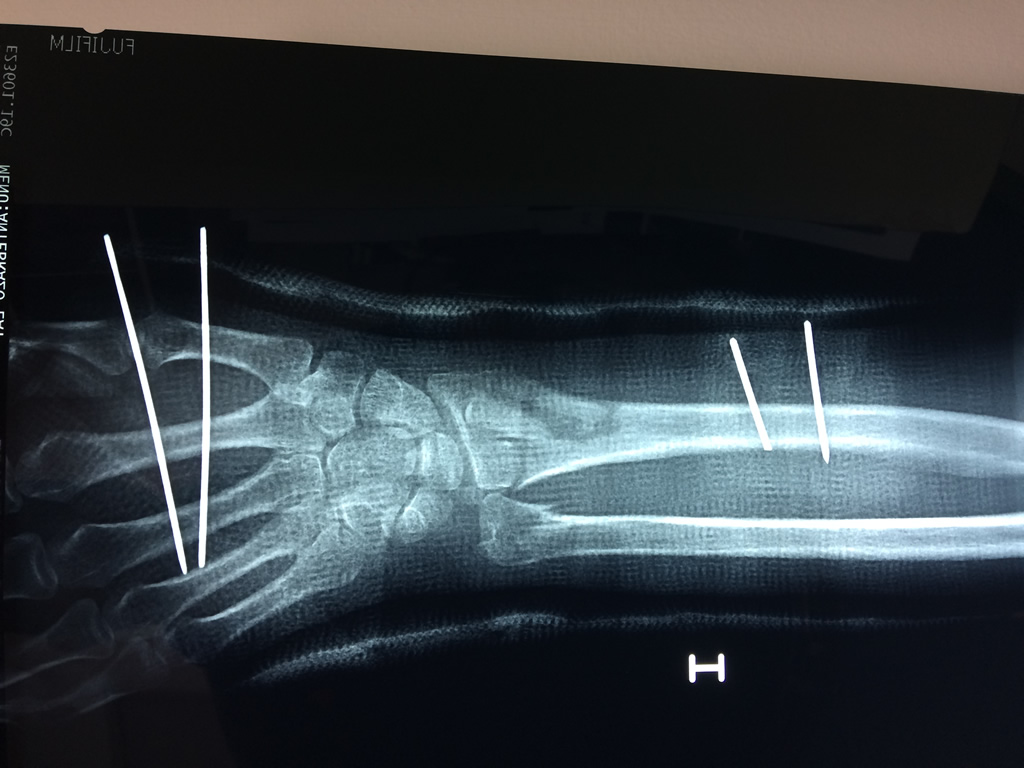

Cirugías de Codos - Cirugías de Muñecas y Manos

Los procedimientos más comunes en cirugía de la mano son aquellos destinados a reparar traumatismos, incluyendo lesiones de tendones, nervios, vasos sanguíneos, y articulaciones; huesos fracturados; y quemaduras, cortes, y otros daños de la piel.